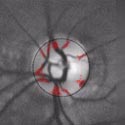

Here are retina images from twins / Ci-dessous deux rétines de jumeaux:

Jumeaux 1 Jumeaux 2

A kind of (circular) barcode is extracted from the pattern of blood vessels, which is stored for further comparison with a new retina image.

Une sorte de code à barres (circulaire) est extrait du réseau vasculaire, qui est stocké afin de permettre plus tard une comparaison avec une nouvelle image de rétine.

First the intensity profile is extracted, then a circular scan is performed to locate blood vessels.

Les lignes de plus fortes intensités sont d'abord extraites, puis un scan circulaire permet d'identifier la localisation des vaisseaux sanguins.